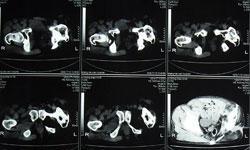

骶髂关节髂骨部下1/2~2/3骨质密度增厚所引起的慢性腰腿痛,称致密性髂骨炎。好发于女性,20~40岁和中年女性多见。患者有复发性下腰痛,有时可向下放射至两侧臀部和大腿,但不是根性疼痛,下腰活动时可加重症状,可能与妊娠、劳损及病灶性炎症有关。